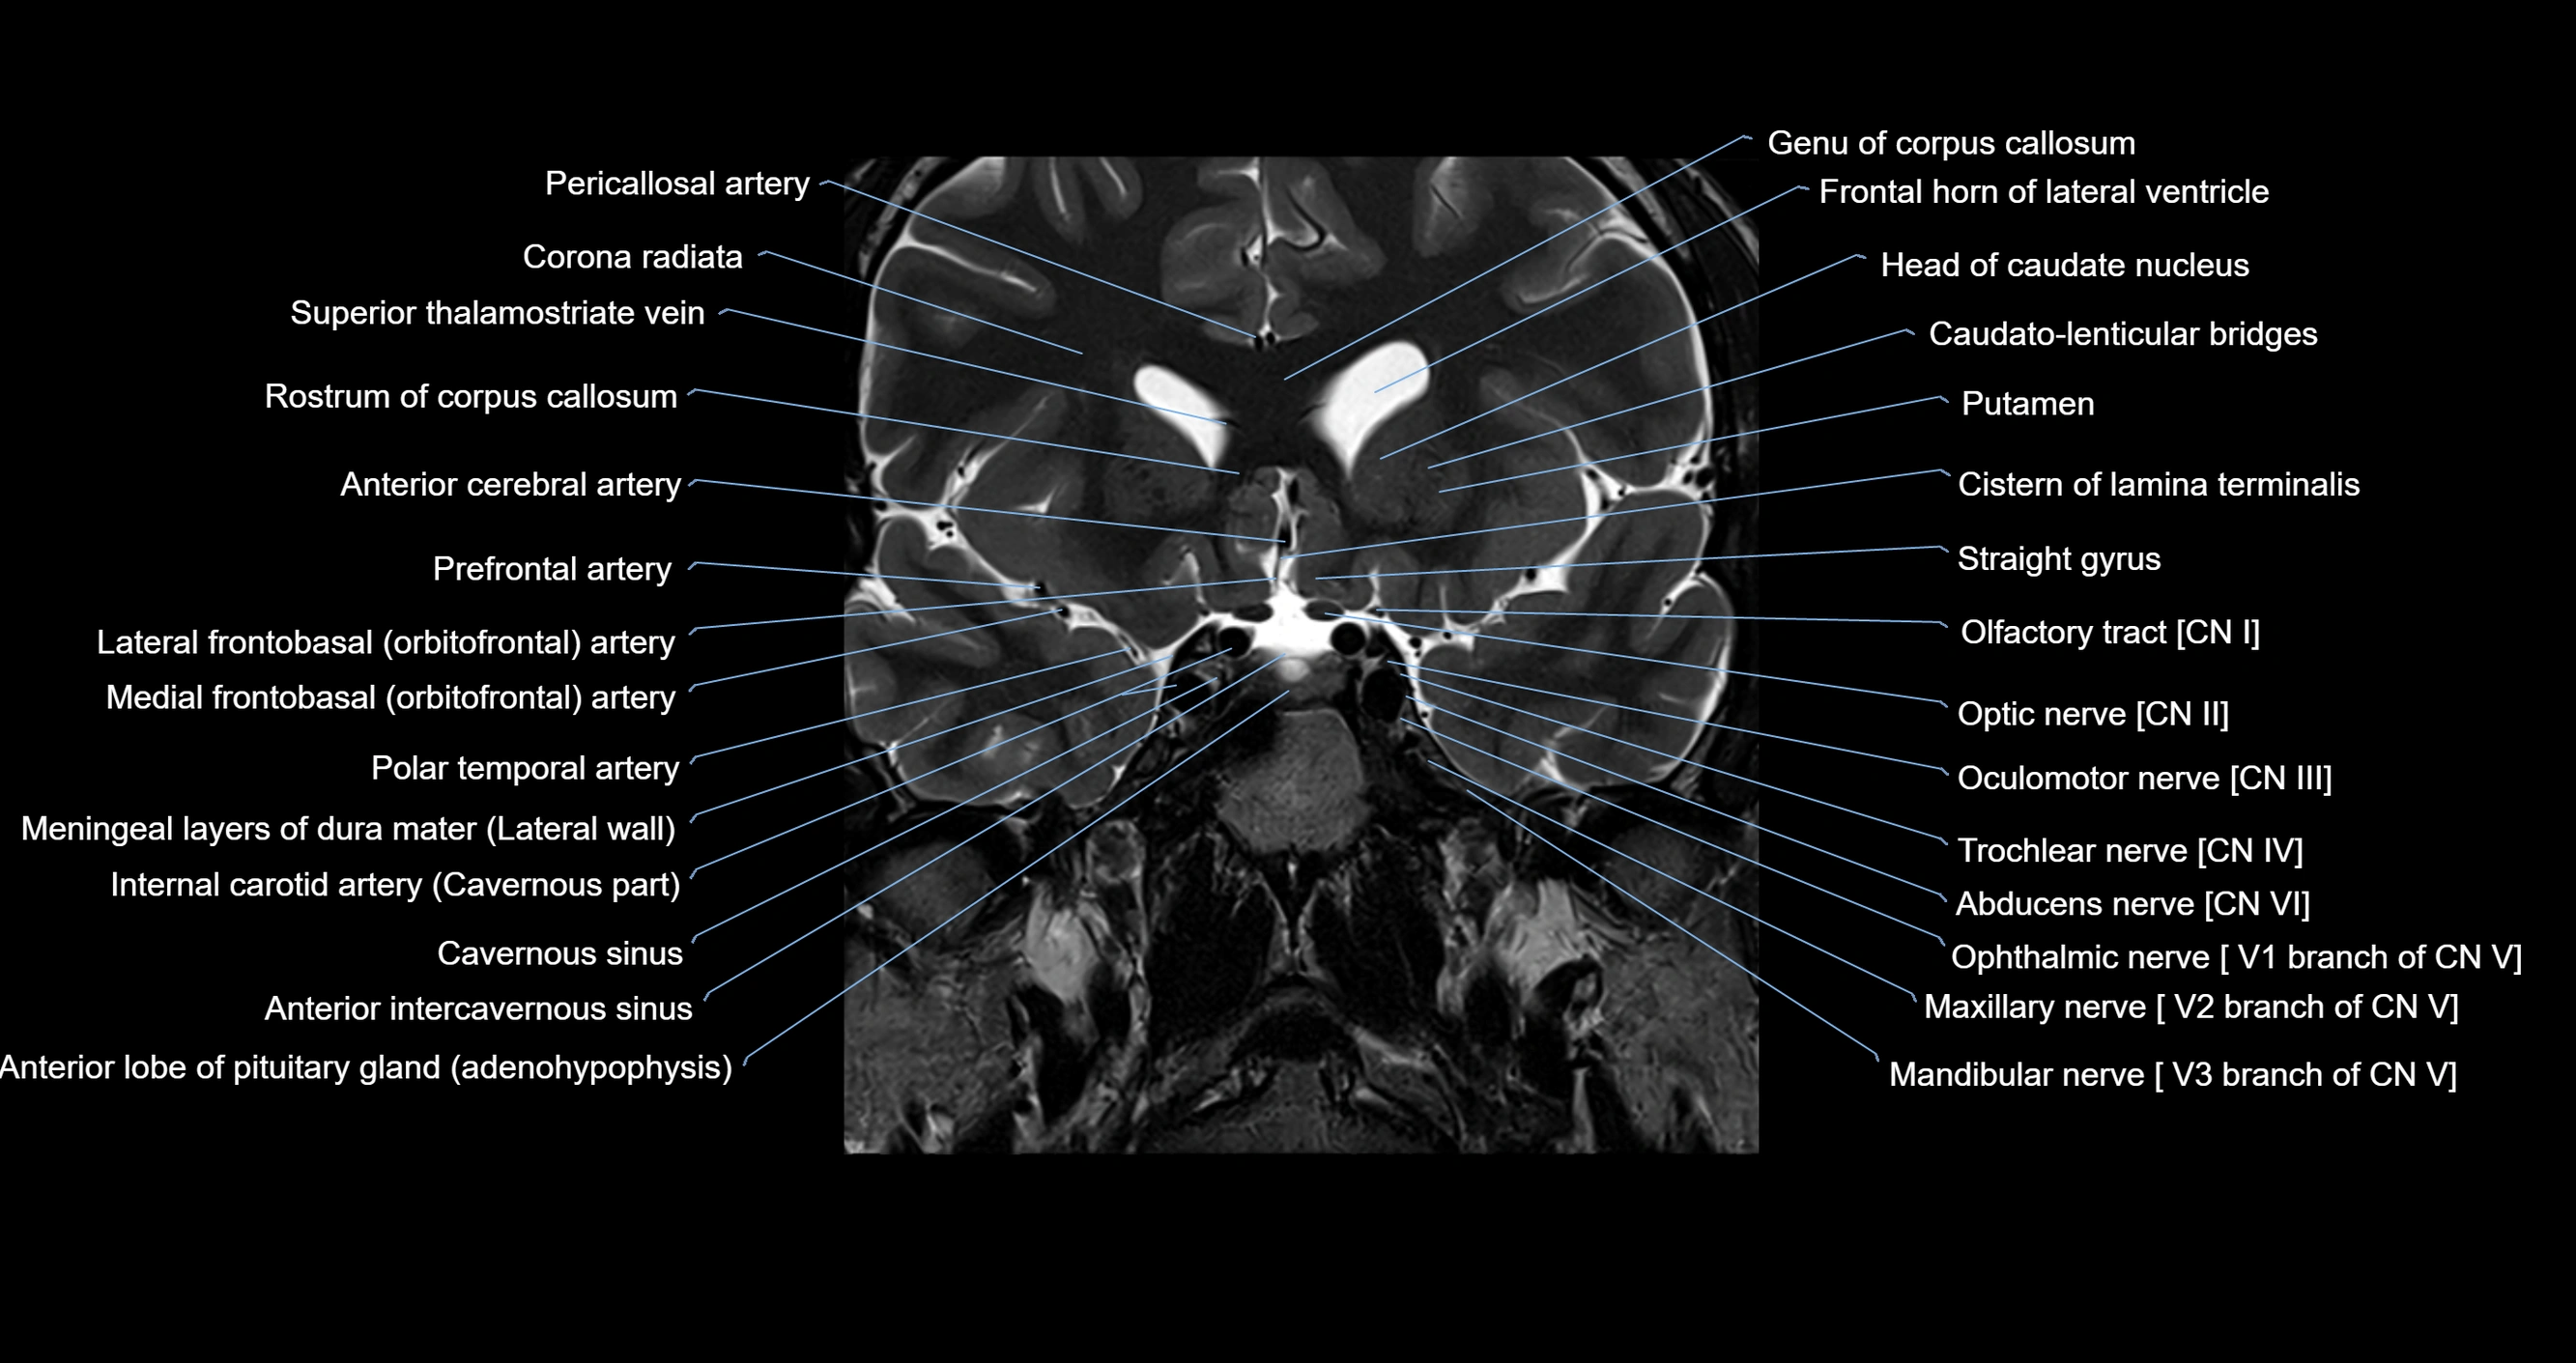

MRI images